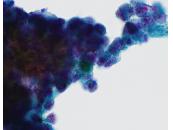

第34回日本臨床細胞学会九州連合会学会(長崎)スライドカンファレンス症例4

種別:甲状腺

出題:野口病院 丸田 淳子 先生

| 年齢 | 89歳 | 性別 | 女性 |

| 採取部位 | 甲状腺右葉腫瘤 | 採取方法 | 穿刺吸引 |

| 検体処理法 | 従来法 |

既往歴:甲状腺機能亢進症(46才,放射線療法後)

現病歴:頚部違和感を自覚,症状改善がないため、当院受診

| 正解 | 4.低分化癌 |

| 1.乳頭癌 | 11件 | (11.3%) | |

| 2.濾胞性腫瘍 | 40件 | (41.2%) | |

| 3.髄様癌 | 22件 | (22.7%) | |

| 4.低分化癌 | 21件 | (21.6%) | |

| 5.悪性リンパ腫 | 3件 | (3.1%) | |

| 投票総数 | 97件 | (100%) |